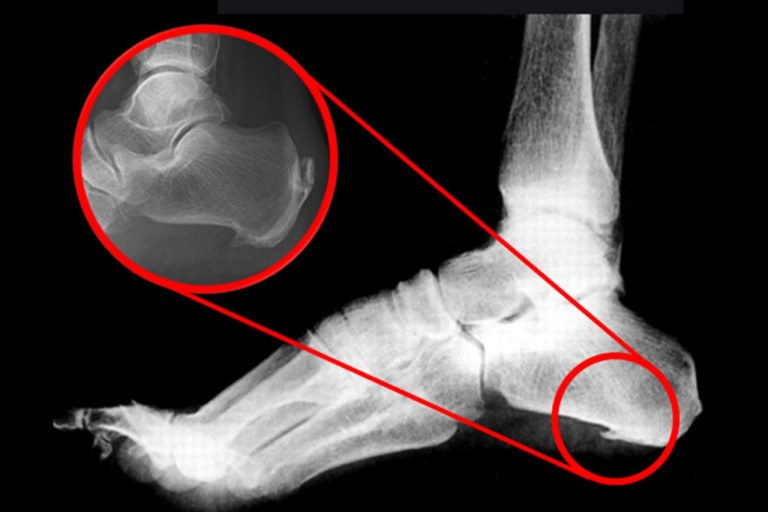

8. 발바닥에 딱딱한 결절

일부 환자들은 발꿈치에 결절이 생길 수 있습니다. 결절은 발꿈치 뼈에 작은 돌출부위로, 족저 근막염이 장기화되면 나타날 수 있습니다. 이 결절은 발꿈치를 눌렀을 때 통증을 유발합니다.